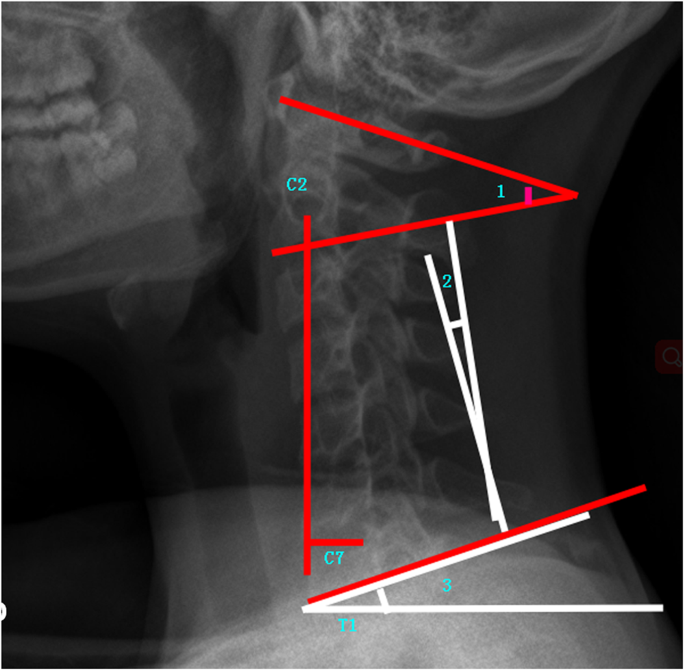

Cervical sagittal alignment parameters: C1-C2 (C1-C2 cervical lordosis, the angle between C1 and the caudal endplate of C2), CL (C2-C7 cervical lordosis is the angle between the caudal endplate of C2 and the caudal endplate of C7), cSVA(cSVA is the horizontal offset from the plumbline dropped from C2 to the posterosuperior corner of C7), TS-CL (T1 Slope minus CL is the difference between T1 Slope and CL) (Fig. 2).

Sagittal lumbosacral parameters: SS, PT, PI, L5 Slope(the angle between a horizontal line and the superior end plate of L5), and L5I (L5 Incidence, the angle between the vertical line and the line connecting the center of the femoral heads axis to the center of the upper endplate of L523) (Fig. 3).